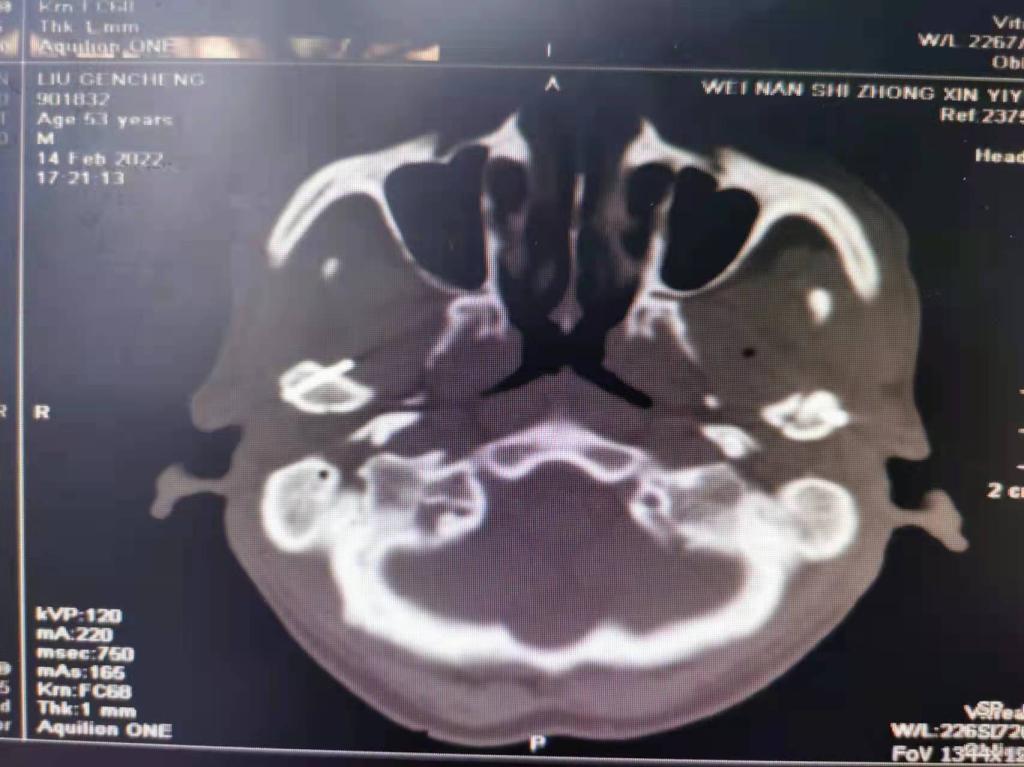

据了解,53岁的患者刘先生在1月25日当天走路不慎摔倒致下颌损伤,造成颏部软组织裂伤和张口困难,前往当地卫生院进行颏部裂伤清创缝合术。术后辗转到渭南市中心医院口腔科门诊就诊,并进行颌面部CT检查提示为下颌颏部正中和双侧髁状突骨折,双侧下颌升支高度不一致,右侧较左侧变短1cm,张口重度困难,咬合关系错乱。刘先生因考虑在春节过后再入院治疗,于2月8日再次前来口腔科以“下颌骨骨折”收治人院。

口腔科主治医师蔺非非为患者入院后进行完善术前常规检查和颌间牵引恢复咬合关系。科主任李瑞春结合患者实际病情和检查结果认为,患者的髁突骨折在下颌骨骨折中所占比例较高,约为17.0%-36.3%。髁突骨折时,耳前区有明显的疼痛,局部肿胀、压痛。通过手指深入外耳道或在髁突部触诊,如张口时髁突运动消失,可能有骨折段移位。双侧低位骨折时,2个髁突均被翼外肌拉向前内方,双侧下颌支被拉向上方,可出现后牙早接触,前牙开秴。髁状突骨折易引起下颌后缩,张口困难,咬合关系错乱,关节强直等并发症。考虑患者系陈旧性骨折应尽早实施手术,避免骨折导致的张口困难、关节强直等并发症。因患者已经错过最佳治疗时期,决定尽快为患者进行手术治疗。

科主任李瑞春和主治医师蔺非非经过缜密的术前讨论和充分评估,手术在全身麻醉下进行,术中克服术野狭小操作不便困难,将下颌骨骨折完好对位,顺利地完成了"双侧髁状突和下颌颏部正中骨折切开复位内固定术"。术后检查患者面部对称,双侧下颌升支高度一致,咬合关系已恢复。